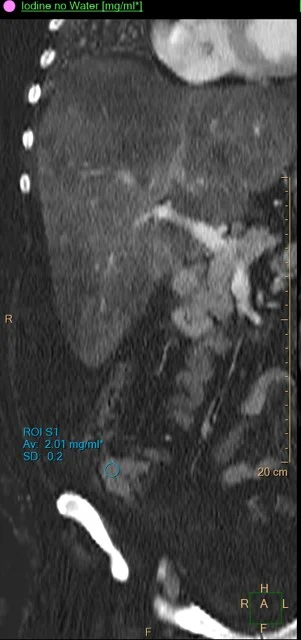

Iodine uptake in cecal mass.